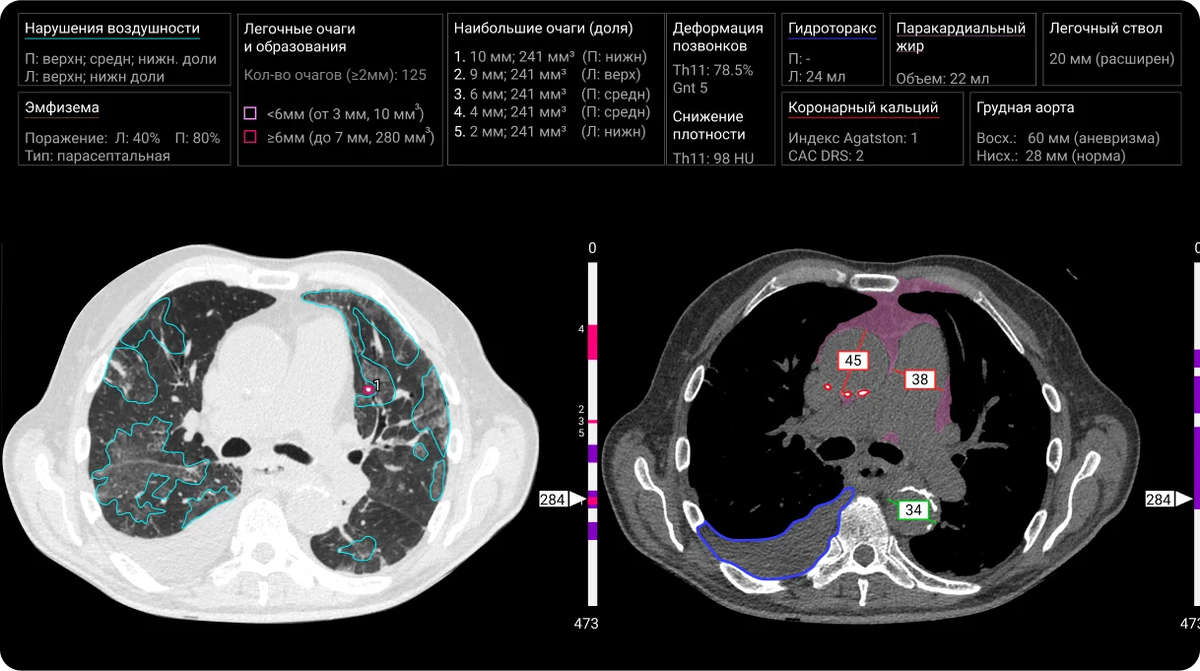

«Третье мнение»: ИИ-диагност для миллионов снимков

В недалёком 2017 году компания запустила ИИ-сервис для анализа оцифрованных мазков крови и костного мозга. Сегодня это один из разработчиков ИИ-сервисов для здравоохранения РФ. Все решения одобрены Росздравнадзором, шесть — включены в реестр отечественного ПО. География охвата — 58 регионов страны.

Один из продуктов — ИИ-сервис для КТ органов грудной клетки. Врач загружает снимок, ИИ-алгоритм распознаёт и описывает его. После обработки специалист получает предварительно заполненный протокол исследования.

Сейчас ИИ-сервисы компании обработали уже более 10 млн исследований, а ежедневно ими пользуются свыше 10 тыс. врачей.